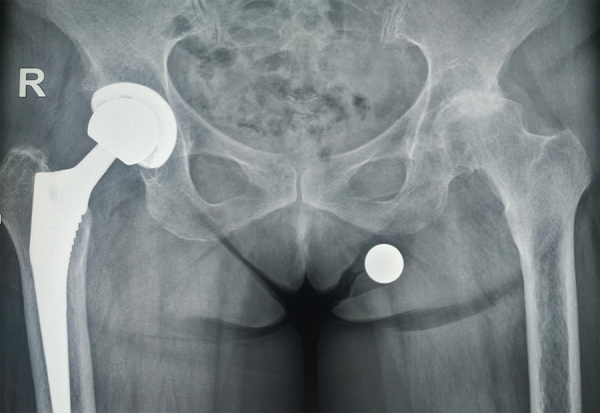

Η ολική αρθροπλαστική ισχίου είναι μια από τις πιο επιτυχημένες επεμβάσεις στον τομέα της ορθοπεδικής, προσφέροντας ανακούφιση από τον πόνο και βελτίωση της κινητικότητας σε ασθενείς με σοβαρή αρθρίτιδα ή εκφυλιστικές παθήσεις του ισχίου.

Η ολική αρθροπλαστική γόνατος είναι μια από τις πιο διαδεδομένες & αποτελεσματικές επεμβάσεις στην ορθοπεδική χειρουργική. Αποτελεί τη λύση για άτομα που υποφέρουν από έντονο πόνο & περιορισμένη κινητικότητα λόγω οστεοαρθρίτιδας κά

Οι αρθροπλαστικές ισχίου και γόνατος είναι από τις πιο επιτυχημένες επεμβάσεις στην ορθοπεδική, προσφέροντας ανακούφιση από τον πόνο και βελτίωση της κινητικότητας. Ωστόσο, υπάρχουν περιπτώσεις..κά